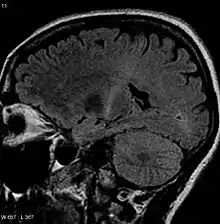

An MRI of the brain (axial FLAIR) looking at a person as if from above that shows increased T2 signal as a small white region within the posterior part of the internal capsule around the center of the image, consistent with the diagnosis of ALS

No single test can provide a definite diagnosis of ALS.[3] Instead, the diagnosis of ALS is primarily based on the symptoms and signs the physician observes in the person and a series of tests to rule out other diseases.[3] Physicians obtain the person's full medical history and usually conduct a neurologic examination at regular intervals to assess whether signs and symptoms such as muscle weakness, atrophy of muscles, hyperreflexia, Babinski's sign, and spasticity are worsening.[3] A number of biomarkers are being studied for the condition, but as of 2023 are not in general medical use.[87]

An MRI of the brain looking at a person from side-on that shows increased T2 signal as a white region in the posterior part of the internal capsule that can be tracked to the motor cortex, consistent with the diagnosis of ALS